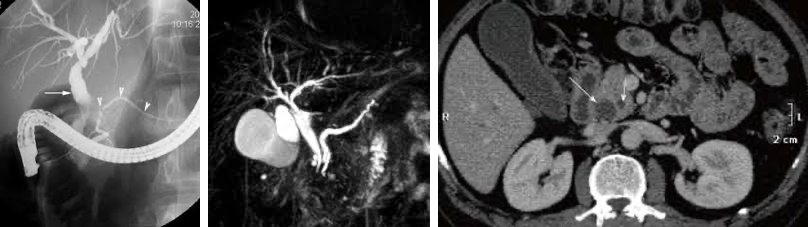

• CT/MRI/MRCP 에서 double duct sign 확인

1) celiac artery encasement 2) SMA encasement 3) SMV encasement